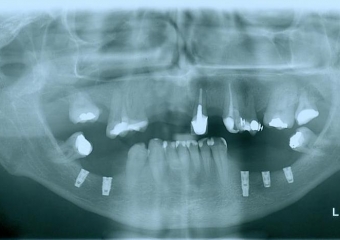

Raio - x implantes inferiores em Junho de 2011  - Clínica Cliniface

Raio - x implantes inferiores em Junho de 2011